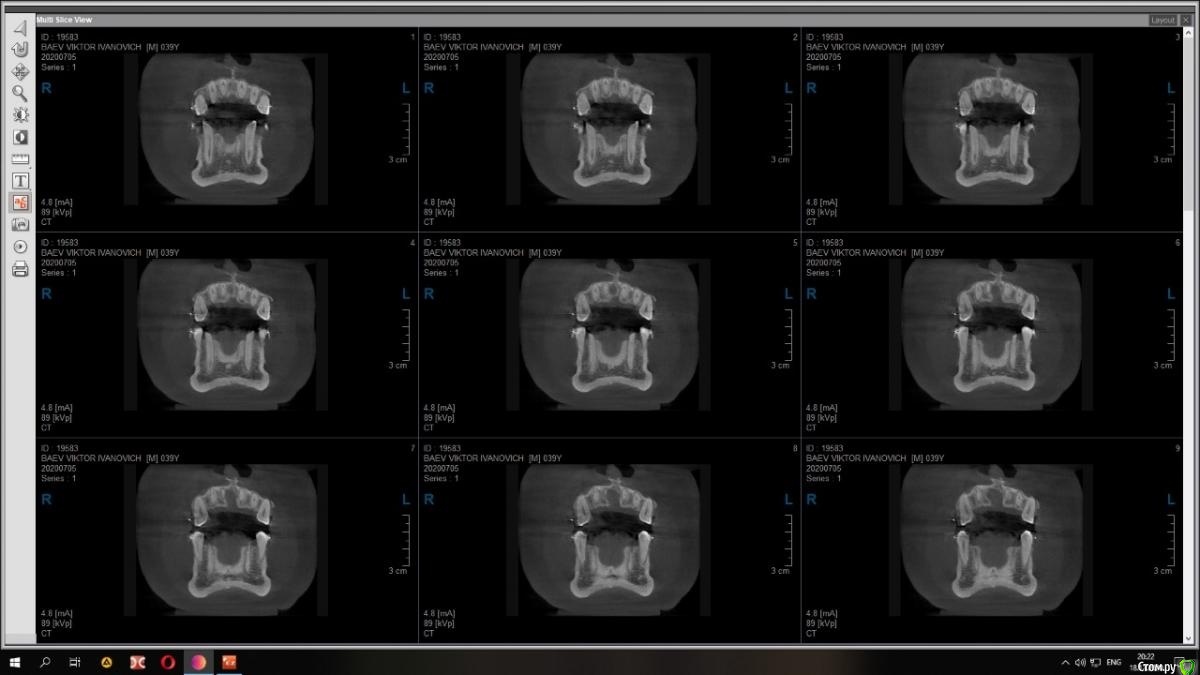

Raystom Опубликовано 15 декабря, 2020 Поделиться Опубликовано 15 декабря, 2020 Случайно на КТ перед имплантацией 36 обнаружили образование. Похоже на кисту резцового канала. Срезы снимка прилагаются.Варианты решения:1. Стационар и ЛОР, т.к. судя по снимку она, на мой взгляд, состоит из 2х частей и есть очень большая вероятность прорастания в носовой ход2. Убирать самостоятельно, но тут возникает очень много вопросов. С нёба доступ самый простой, но потом непонятно как закрыть костный дефект так, чтобы была возможность восстановления кости. При вестибулярном доступе предварительно придется делать эндо 111 с последующей резекцией, но, непонятно, удастся ли его вообще сохранить. Ещё момент, если убрать только обширную часть (нижний компонент), положить резорбируемую мембрану на дно, а аугментат через 2 месяца, дабы не пророс. При этом верхний компонент убрать с помощью ЛОР-эндоскопии.И организационный вопрос, как будет лучше, как и планировалось провести имплантацию 36, дать человеку отдохнуть на новогодних праздниках, а после уже лечение по поводу кисты Ссылка на комментарий

Raystom Опубликовано 21 декабря, 2020 Автор Поделиться Опубликовано 21 декабря, 2020 Киста то малюсенькая. Вскрыть и почистить. Нёбно конечно же. Можно положить мембрану, в полость ничего не класть. В нос я бы вообще пока не лез. меня смущает 3 момента, первый это то, что она прилетит рядом с апикальной частью 11, второй это то, что мне показалось она состоит из 2х частей и третье, это то, что она около 1см в диаметре (просто пока она не выросла и натворила дел, с ней можно что-то сделать) плюс ко всему стоят брекеты и мне кажется это может ускорить процесс роста кисты Ссылка на комментарий